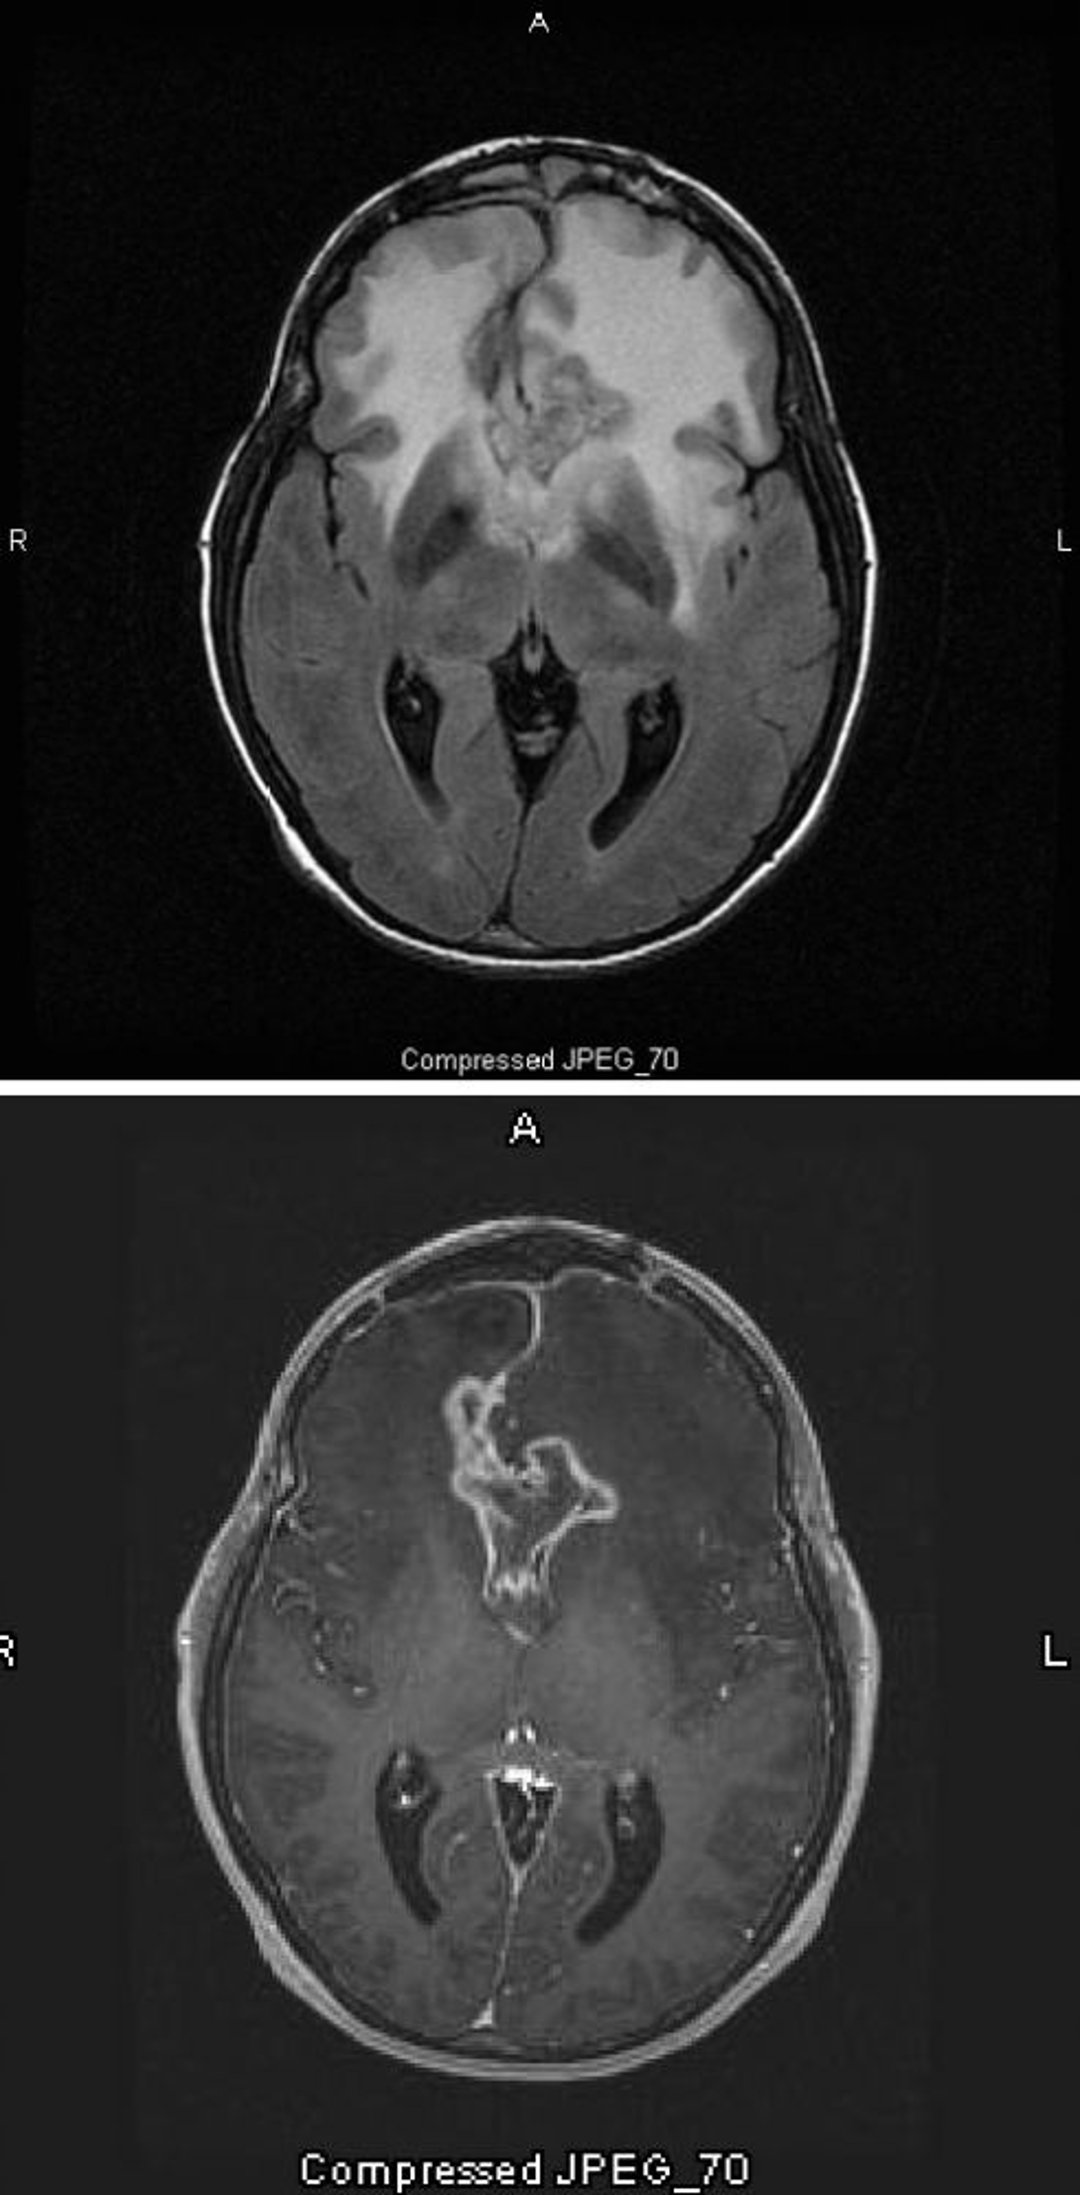

Glioblastoma

La resonancia magnética T2-FLAIR (arriba) muestra una gran señal blanca bilateral (hiperdensidad) alrededor de un glioblastoma, que es el astrocitoma de mayor grado y más maligno. Este glioblastoma en particular se denomina glioma en mariposa porque la señal blanca alrededor del tumor tiene la forma de las alas de una mariposa; es causado por el edema cerebral. En el estudio ponderado en T1 (abajo), el contraste delinea el borde del tumor (refuerzo anular). El edema aparece como un área oscura (hipointensidad) en T1.

Images courtesy of William R. Shapiro, MD.